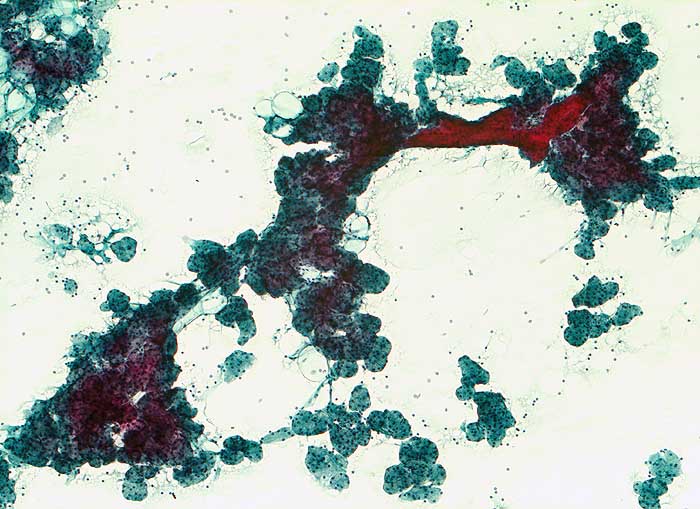

Sialadenose

Hyperplasie / Hypertrophie

Parotis

Feinnadelpunktion Parotis: hypertrophe runde Drüsenazini mit rotem Schaltstück. Die Azinuszellen sind deutlich vergrössert zytoplasmareich.

Histologie: Chronische obstruktive Sialadenitis mit Fibrose und Atrophie der Drüsenazini

Endokarditis. Kathetersepsis. Leberzirrhose. Parotisschwellung beidseits.

Nicht neoplastische Vergrösserung der Speicheldrüsen. Zytologisch lässt sich die Diagnose aufgrund des klinischen Hintergrundes und des Fehlens neoplastischer oder entzündlicher Veränderungen stellen.